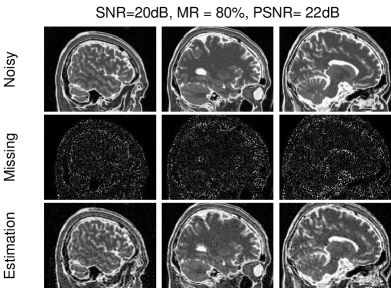

[Uncaptioned image] Andrzej Cichocki received the Ph.D. and Dr.Sc. (Habilitation) degrees, all in electrical engineering, from Warsaw University of Technology (Poland). He is the senior team leader of the Laboratory for Advanced Brain Signal Processing, at RIKEN BSI (Japan). He is coauthor of more than 400 scientific papers and 4 monographs (two of them translated to Chinese). He served as AE of IEEE Trans. on Signal Processing, TNNLS, Cybernetics and J. of Neuroscience Methods.